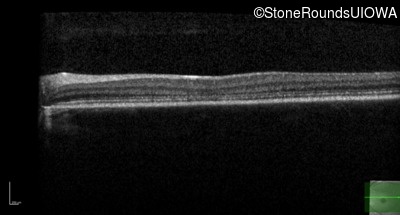

Infrared Fundus Photograph - Right - 20/80 -1

Exemplar